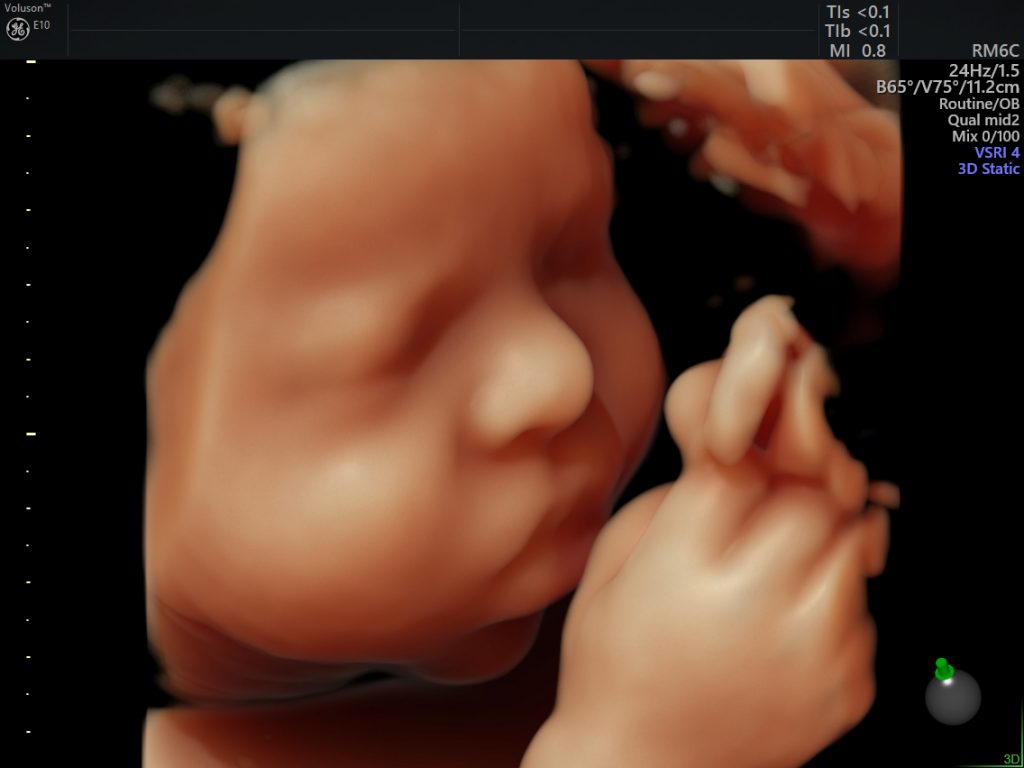

width= Above: Ana Paula Silveira and Alvaro Zermiani are both legally blind. But they were able to touch the face of their son, Davi, when he still in his mother's womb. Ana Paula's doctor used data from GE's Voluson E10 machine to 3D print the fetus. Image credit: Ana Paula Silveira and Alvaro Zermiani. Top: An image captured by the Voluson E10 machine. Image credit: GE Healthcare.

Today, clinicians use the technology to see the human body in incredible ways. Gone are the grainy images most expectant parents carried in their wallets as recently as five years ago. The latest machines like the Voluson E10 from GE Healthcare can produce images in 4D — three spatial dimensions plus time. They can also export data to a 3D printer to enhance conversations around surgical planning, or allow blind parents to “meet” their child.

width= A fetal hand at 29 weeks. Image credit: GE Healthcare.

width= The fetus at 14 weeks. Image credit: GE Healthcare.

width= The fetus at 38 weeks. Images credit: GE Healthcare.